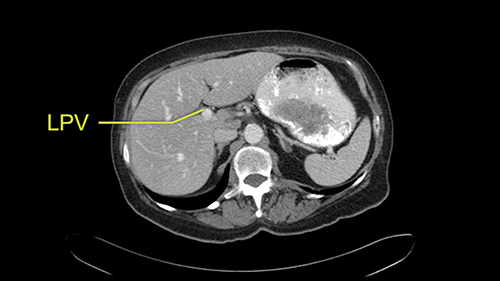

The procedure-specific slowing down moments from a technical point of view for a right hemihepatectomy include a careful evaluation of the inflow structures including the right hepatic artery, the right portal vein, as well to make sure that I have identified and preserved the left hepatic artery and the left portal vein at all times, and minimize any injury or dissection of the common bile duct. Also, I am careful when I mobilize the right liver, not to tear the right triangular ligament and cause bleeding of the liver as I mobilize it off the retroperitoneum and the bare area. In addition, the last procedure-specific slowing down moment is to carefully identify the right hepatic vein and ensure that I encircle it safely without damaging the IVC or the middle and left hepatic vein structures at all times.

In addition, as I plan this operation, I will also look at the size of the small tumors. They’re very small, some are less than one centimetre in size, and carefully evaluate the relationship between the small tumors and the surrounding vascular structures. If I cannot see or feel the tumors at the time of surgery, I will use the blood vessels in order to landmark and plan my operation.

![[RHA]](jpg/preop_sg_moment3.jpg)

The only other most important feature that I usually consider is the portal vein split or the bifurcation, especially if doing a major liver resection like a right lobe. I like to look at the length of the common right portal vein trunk which looks like its probably long enough to put a stapler on. Final decision would be in the OR. If it wasn’t long enough and I was concerned about injuring the bifurcation or the left portal vein, then I would divide the Segment 5-8 and 6-7 portal tracks individually.

![[LPV]](jpg/preop_sg_moment4b.jpg)

This patient has an interesting minor anomaly with what looks like a Segment 7 portal vein coming off close to the bifurcation of the right portal vein but again if I was doing a right lobe which is my plan, this wouldn’t be an issue.